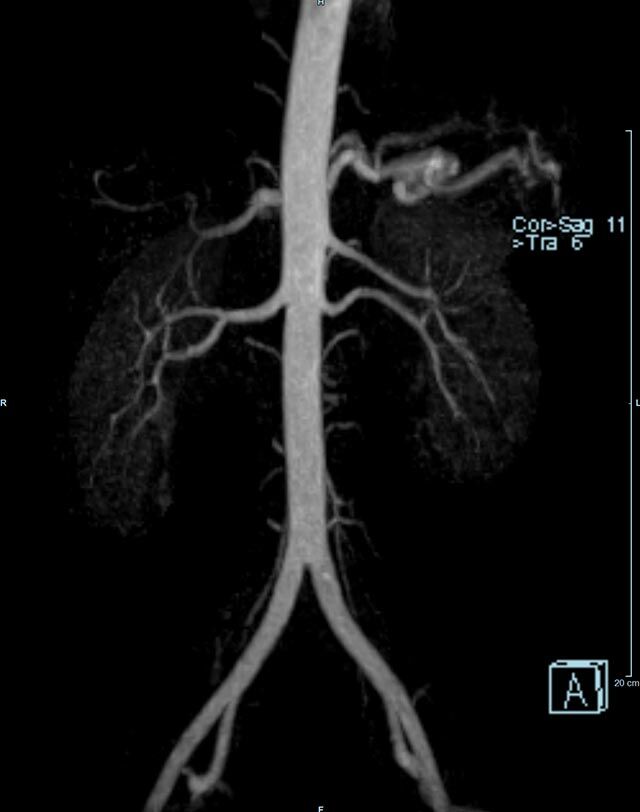

Aorta

• Bauchgefäße

• Erfassung und Verlaufskontrolle bei arteriellen Aneurysmen (Aussackungen der Arterien), vor allem der Bauchaorta

• Darstellung von Gefäßengen an Nierenarterien, Baucharterien und Becken-/Beinarterien

Ganzkörper Angiographie mit Kontrastmittel

• MR-Angiographie mit Kontrastmittel

• Erfassung arterieller und venöser Gefäße/Bypässe aller Körperregionen mit 3D-Rekonstruktion

• je nach klinischer Fragestellung zeitaufgelöste MR-Angiographie (4D-MRA) z.B. bei Frage arteriovenöse Fistel/ Shunt oder Darstellung Unterschenkelarterien vor geplanter Bypassoperation.